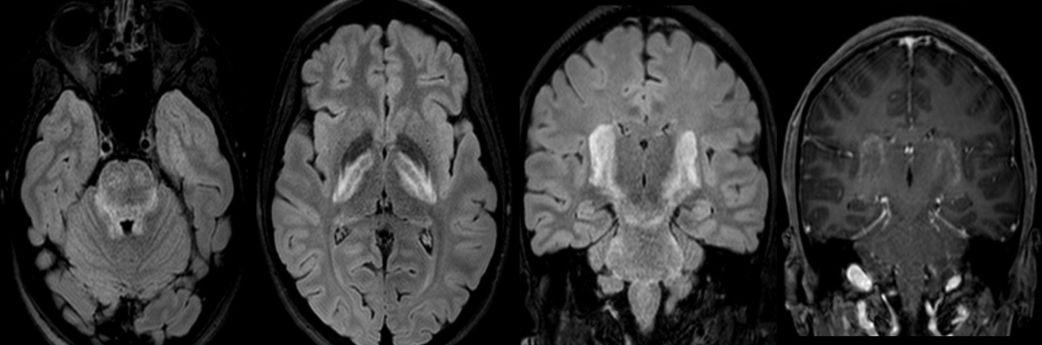

患者,女,18岁。主要症状为急性头痛、呕吐、视物模糊。患者既往有炎症性肠病和口腔溃疡病史。

答案:神经白塞病

本病例开始没有给炎症性肠病和口腔溃疡病史,好多老师考虑是中毒。当一个既往有反复口腔或生殖器溃疡、葡萄膜炎或白塞病其它症状的患者出现神经系统症状时,需要考虑神经白塞病(NBD)。神经白塞病是一种累及多系统的自身免疫性疾病。临床表现为复方性口腔溃疡、生殖器溃疡、皮肤病变和葡萄膜眼,也可累及血管、神经系统、消化道、关节、肺、肾等器官。当累及神经系统时,称为神经白塞病。中枢神经系统受累较多见,可有头痛、Horner综合征、假性球麻痹、癫痫、无菌性脑膜炎、视乳头水肿、偏瘫、失语、截瘫、感觉障碍、精神异常等症状。脑实质NBD典型的好发病灶是脑干,通常累及脑桥,可向上蔓延至中脑、基底节、间脑;可表现为半球的白质病变,也可为半球孤立性病灶,需与肿瘤、脓肿和先天性囊肿等鉴别;急性/亚急性病灶为T1WI上等-低信号,增强通常有强化,T2WI和FLAIR上为高信号,DWI上高信号,相应ADC值降低。